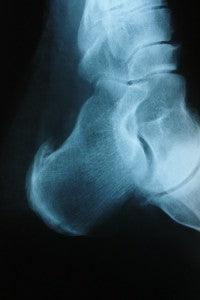

Heel spurs can be extremely painful, basically causing the ligament that attaches to your foot (the plantar fascia) to separate from the hell bone. The condition is caused by excessive bone growth on the heel and can affect both athletes and non-athletes. But how do you know that you actually have it? Here are some ways to find out, plus some ways to deal with the problem.